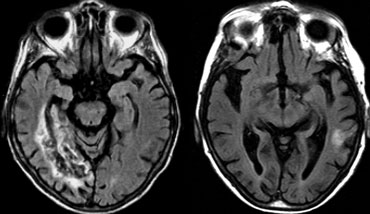

FTLD: T2WI and FLAIR with 'knife blade' atrophy of left temporal lobe with normal right temporal lobe FTLD: T2WI and FLAIR with 'knife blade' atrophy of left temporal lobe with normal right temporal lobe

The images are of a patient with progressive aphasia.

The most prominent finding is the striking asymmetric atrophy of the temporal lobe on the left side with not only atrophy of the hippocampus, but also the temporal poles.

The atrophy has resulted in gyri that appear as sharp as knives ('knife blade atrophy').

There is also some increased signal intensity seen on the FLAIR image, probably due to gliosis.

These findings are pathognomonic for the diagnosis of FTLD.

Patients with left-sided temporal atrophy are usually clinically obvious.

Right-sided atrophy is usually not as easily recognized as these patients only present with subtle disturbances in recognizing faces.